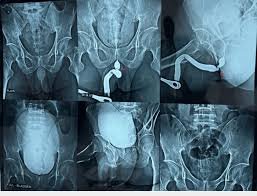

We provide quick and accurate Emergency Sonography, X-Ray, and Doppler services for immediate diagnosis.